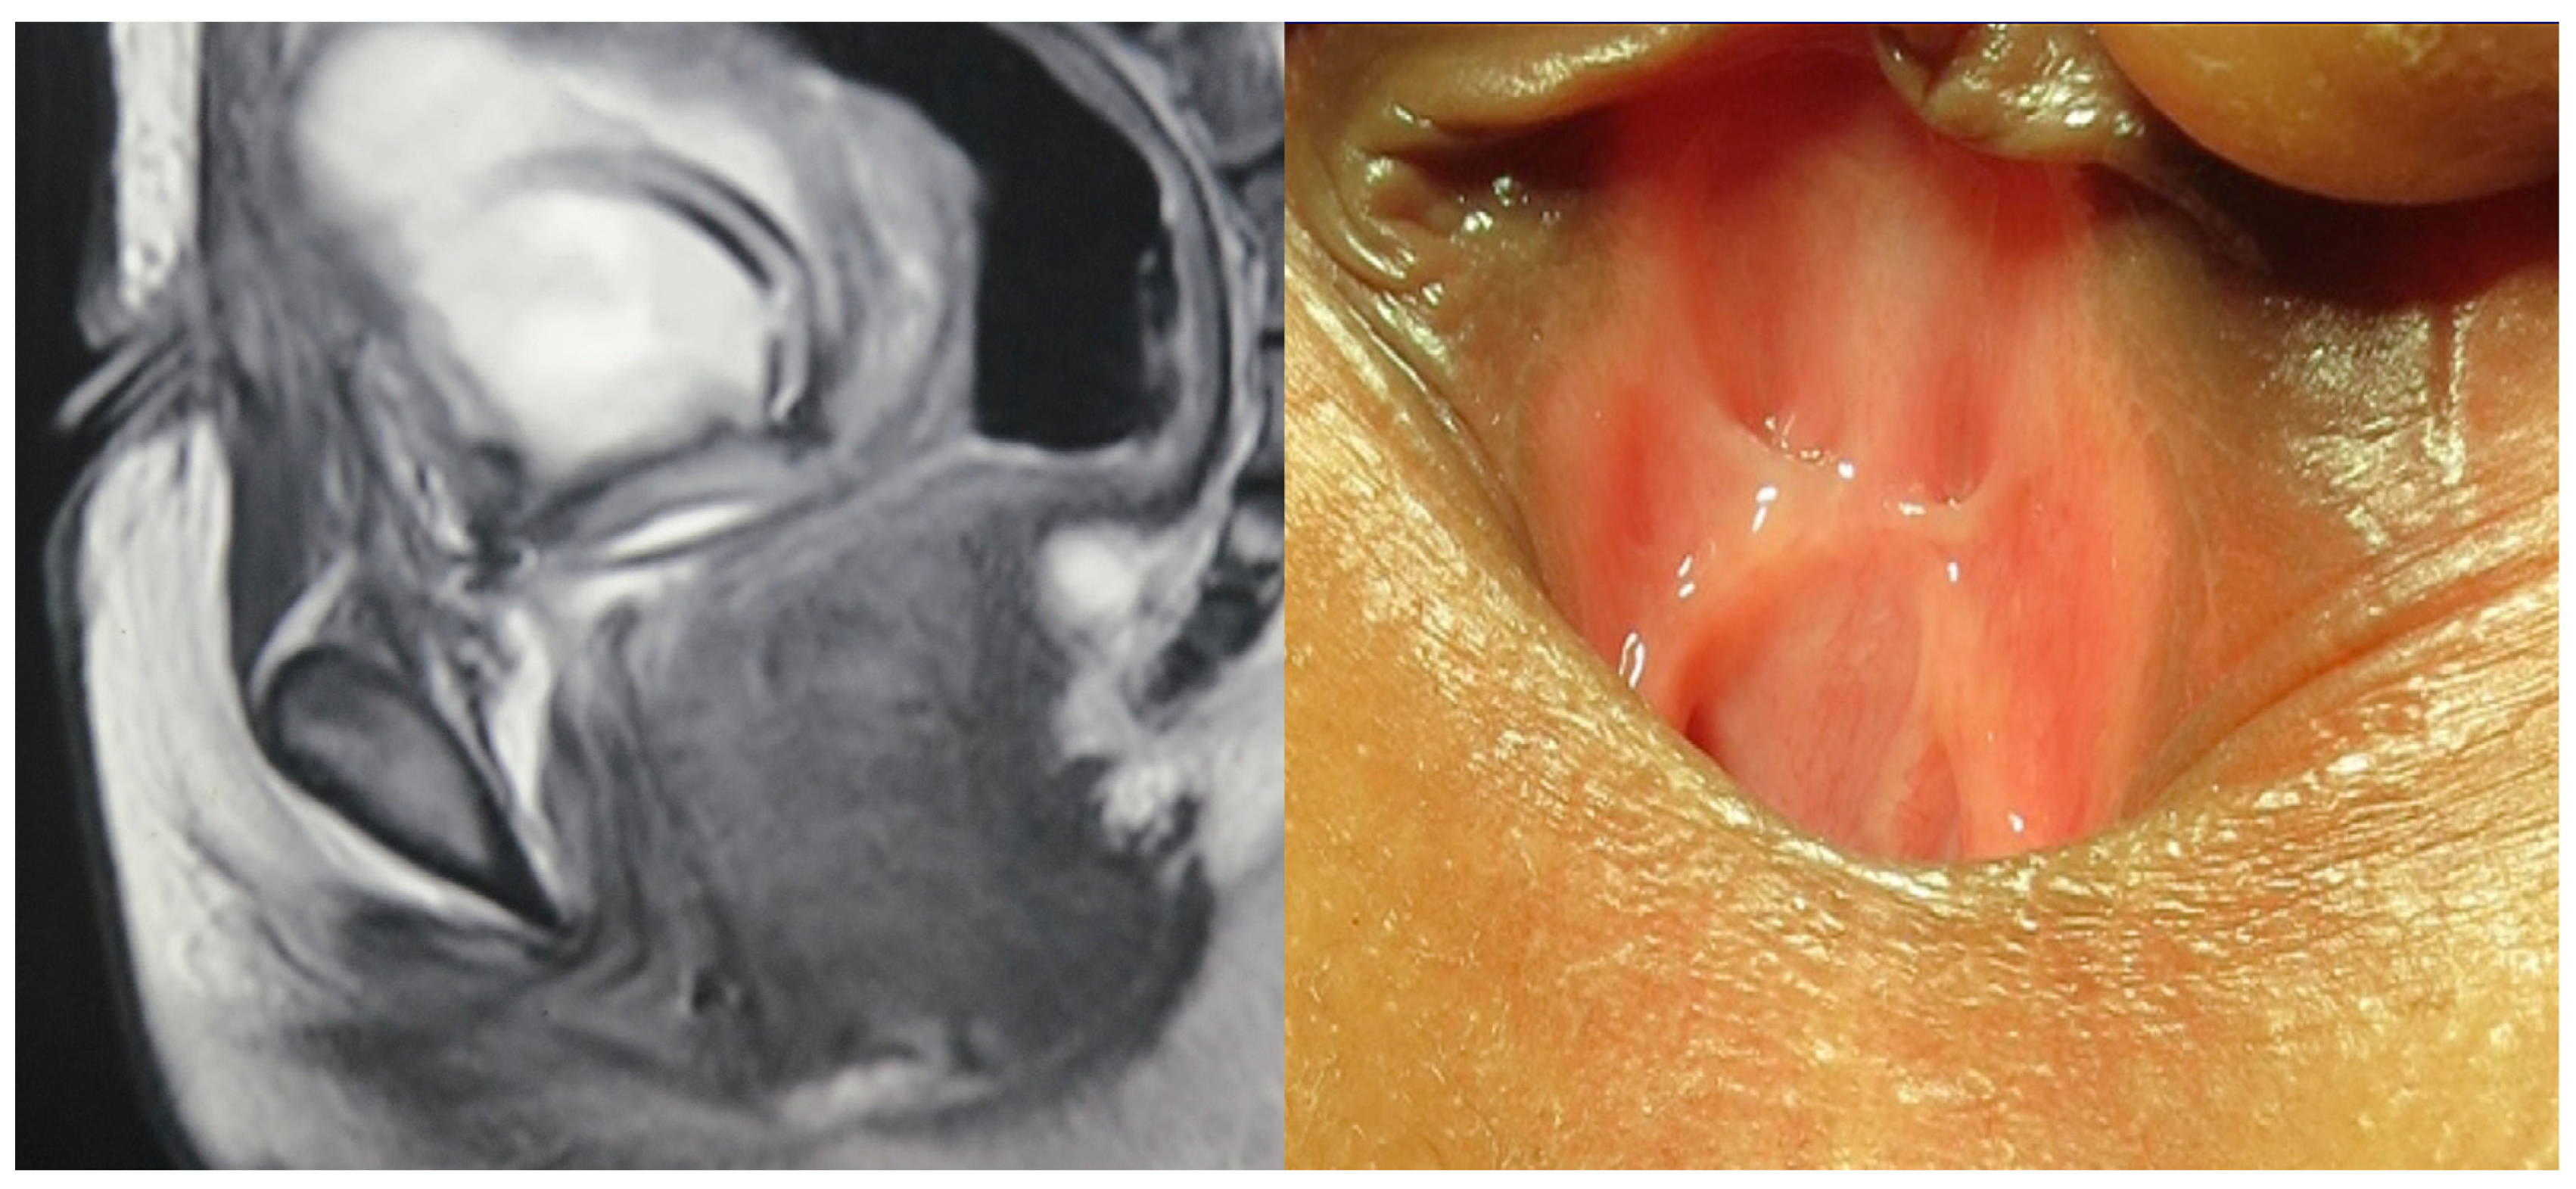

Urethrovaginal fistula should be suspected in every female patient with PFUI, and we found a urethrovaginal fistula in most of our patients. If possible, a guide wire was passed through the urethra into the bladder with the outside end brought out through the introitus. Subsequently, we performed a vaginoscopy, which usually showed a normal vagina with visualization of the cervix (Figure 3), a post-traumatic transverse vaginal septum preventing visualization of the cervix, or stenosis of the vagina at the site of trauma.

Figure 3.

Vaginoscopy demonstrating cervix.